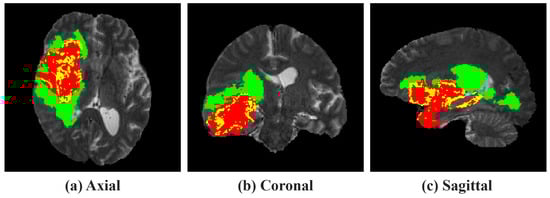

Figure 7 illustrates the tumor segmentation outputs of the TACR module across various anatomical orientations on the BraTS 2020 dataset. From left to right, each column shows the segmentation results with the TACR module aligned separately in the axial, coronal, and sagittal orientations, followed by the integrated approach using all three orientations, and finally, the ground truth for comparison. In the visualization results, the performance of the NCR/NET regions, marked in red, and the ED region, highlighted in green, was inaccurately predicted by all models except for the one integrating all three orientations. Specifically, in the first row, models exclusively employing axial, coronal, or sagittal orientations incorrectly identified normal tissue as ED in the same slice, and a review of the 3D-rendered results revealed a failure to predict within NCR/NET regions. Furthermore, in the second row, all models, except the one integrating all three orientations, incorrectly identified normal tissue as the ED region.

Figure 7.

Visual comparison of tumor segmentation outputs from the TACR module across different anatomical orientations on the BraTS 2020 dataset. The colors indicate regions of tumors. Red: NCR/NET; yellow: ET; green: ED.